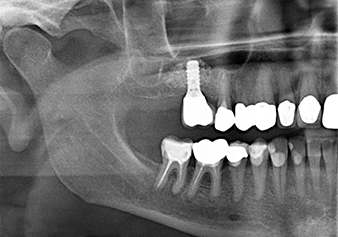

To move the augmentation material in the direction of the maxillary sinus atraumatically, the implant was inserted very slowly by hand (Fig. 9). In the process, the membrane was pushed in the cranial direction once again. After two months, the surgical site healed without irritation. Six months later, the x-ray check showed a significant increase in opacity as an indication of ossification (Fig. 10). The prosthetic restoration was carried out with a metal-ceramic crown.

The x-ray check shows a largely homogeneous peri-implant hard tissue structure

Fig.10: A good six months later, after the definitive crown had been incorporated, the x-ray check shows a largely homogeneous peri-implant hard tissue structure.